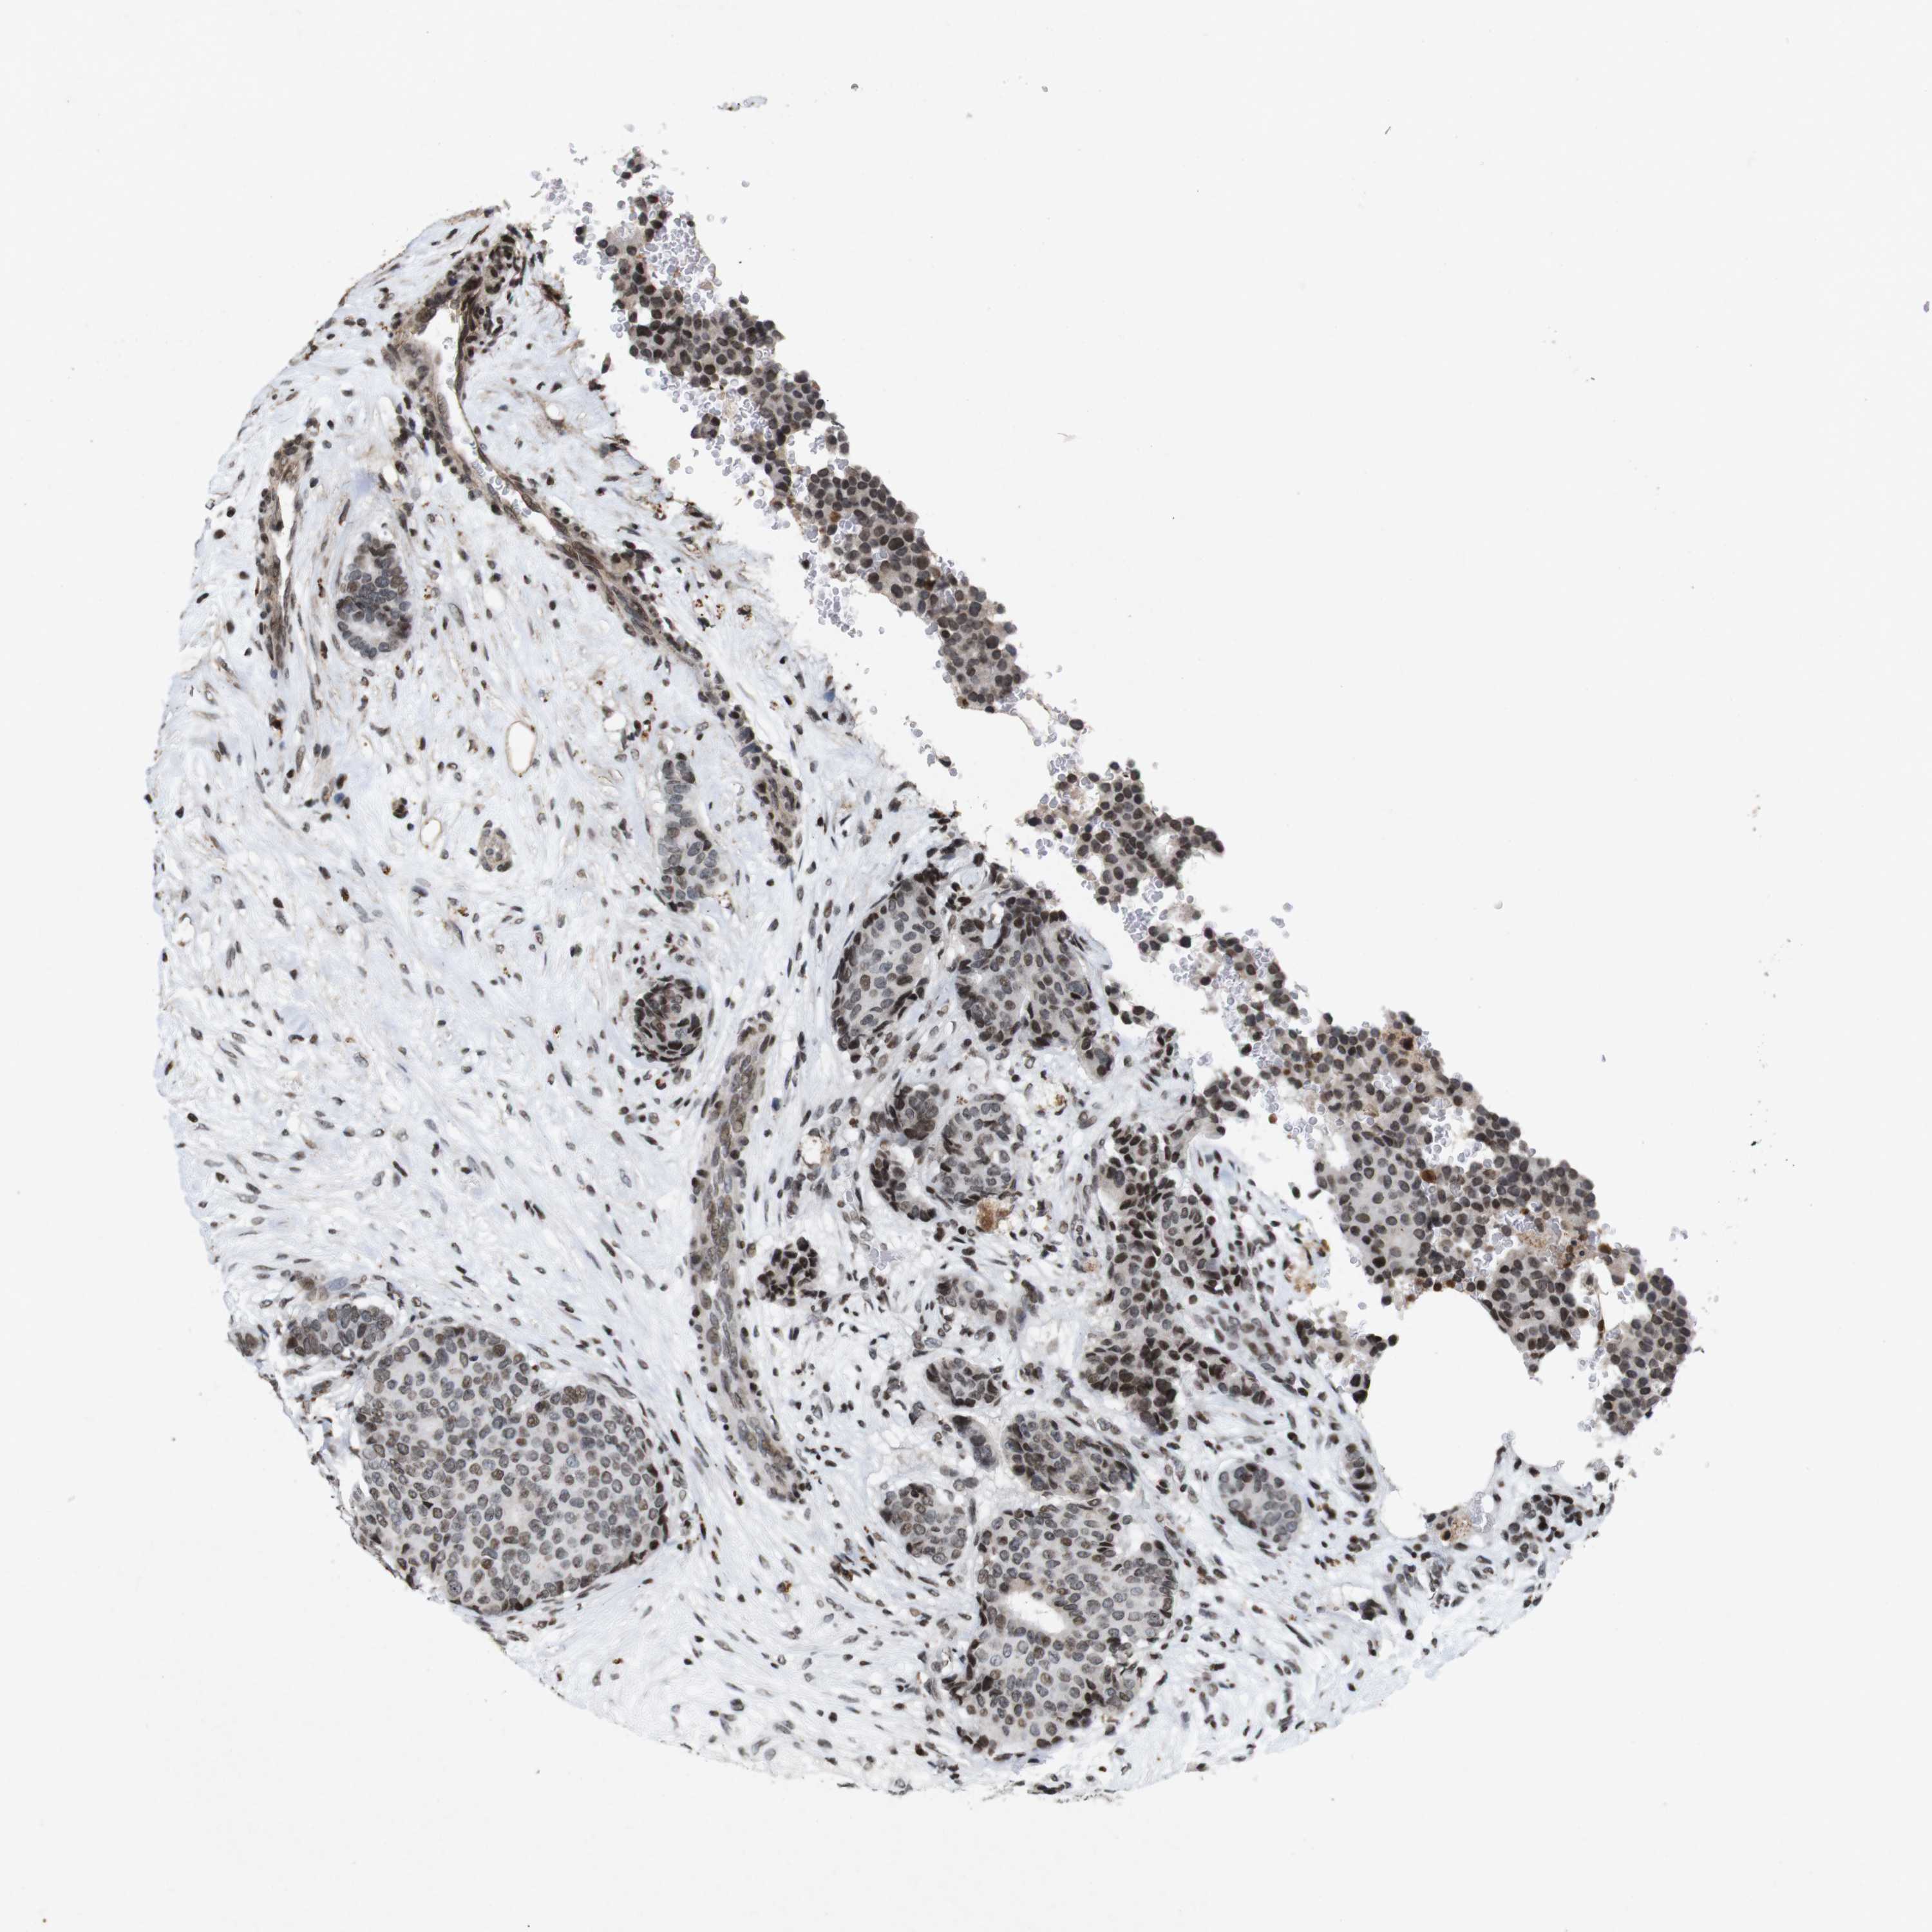

CANCER BREAST CANCER Show tissue menu

BRCA TCGA BRCA VALIDATION PROTEIN EXPRESSION

Breast cancer

Human cancer